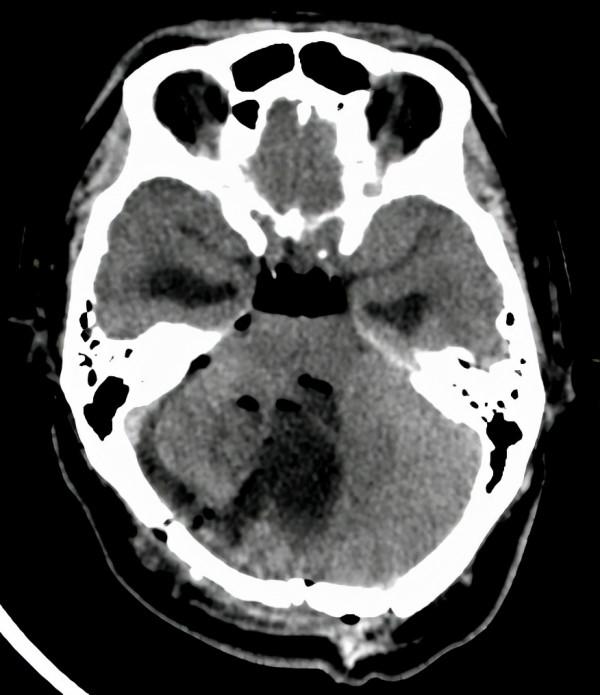

影像檢查顯示:右側小腦巨大囊實性佔位,形似“戒指”。

“它的內部大部分是液體,像是裝滿水的氣球,在一端的結節才是罪魁禍首。只要找到並切除了結節,其他看似很大的部分,也就不足為懼了。”穆林森形象地比喻道:“這個腫瘤形狀看起來確實像‘戒指’,它看著雖大,其實只有那個‘發亮的寶石’才是手術切除的關鍵。至於其它部分,就像是‘紙老虎’,一捅就破。”

術後複查CT